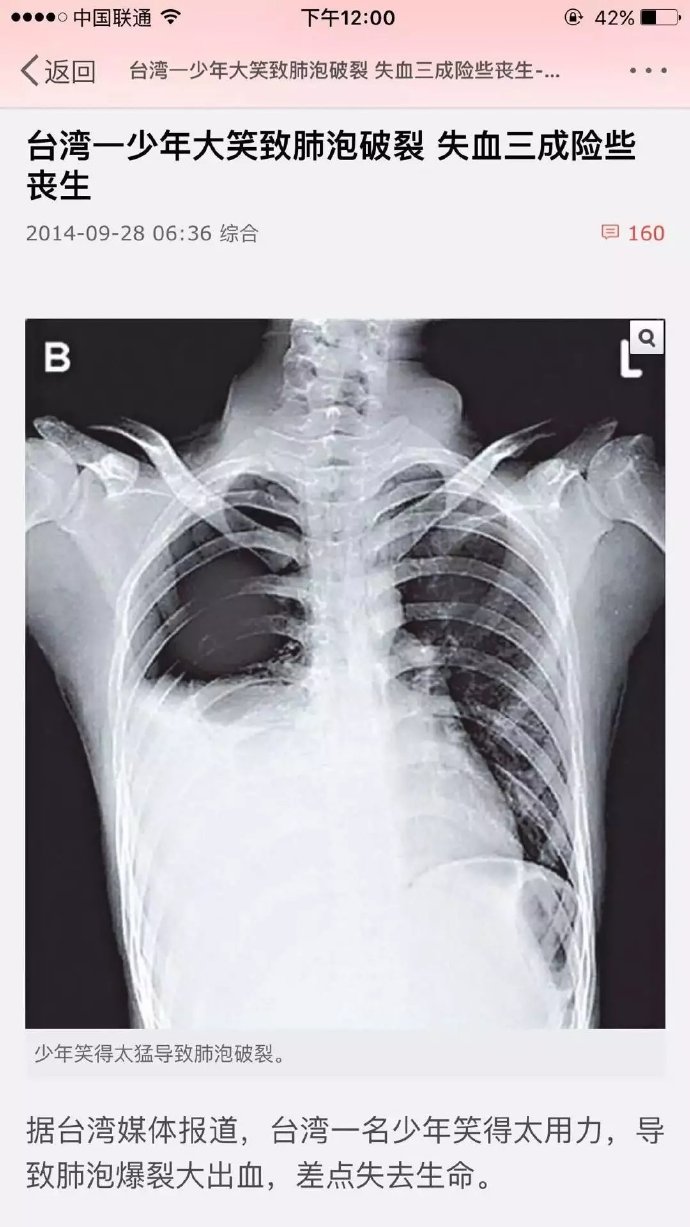

原来真会笑死人的!

1.jpg

(101.46 KB)

2016-9-12 09:21